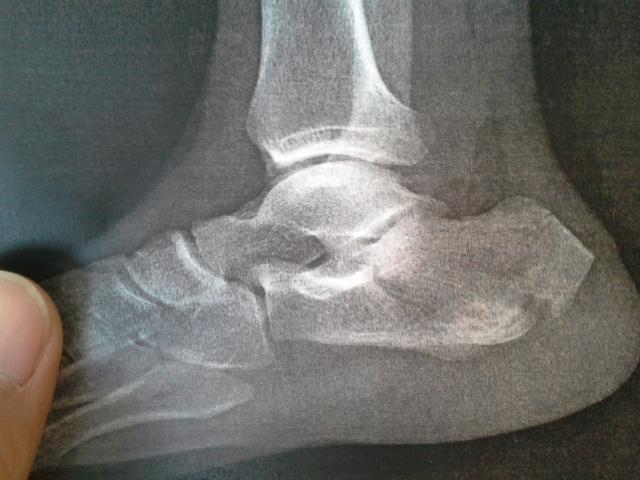

跟骨骨折切开复位钢板内固定术

病例讨论跟骨骨折

跟骨骨折